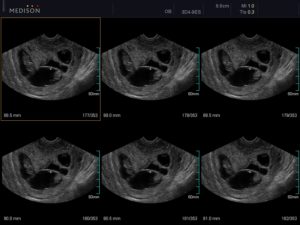

Узи двойни при беременности: фото на ранних сроках в 5-6 недель и позже

Определение двойняшек и близнецов осуществляется таким продуктивным методом исследования, как УЗИ. Этот вид обследования обеспечивает информацией о месте расположения ребенка, имеется ли многоплодная беременность и др.

Как правило, двое эмбрионов четко определяют на УЗИ с самых ранних недель — 5-7. Позже врач способен это определить и без применения ультразвуковой диагностики. Двойняшек можно выявить по такому признаку, как увеличенный размер матки, уже с ранних сроков, а медицинская диагностика с применением ультразвука покажет двух детей только на 1 скрининге — в 10-14 недель.

Двойняшки покажутся на УЗИ уже с 5 недели

В таком случае УЗИ эмбрионов покажет наличие двойни уже на 5 неделе, особенно с применением высокочувствительных датчиков 3д-сканирования. Осмотр дает возможность определить двойняшек только на сроке 9-11 недель.

Следовательно, наличие двойняшек в утробе выявляется посредством ультразвука уже через месяц после зачатия, на снимке они выглядят как 2 образования темного цвета внутри полости матки (см. фото УЗИ-обследования двойни ниже).

- УЗИ-диагностика двойни через 11 недель показывает немного уменьшенные для своего срока развития размеры первого и второго плода – примерно 4,2-4,8 см.

- При обследовании на 12 неделе эмбрионы имеют длину по 6 см, а их вес составляет примерно 8 грамм.

Считается, что точно увидеть несколько эмбрионов, можно только при помощи УЗИ. На каком сроке определяют многоплодную беременность? Специалист может увидеть данный факт в 5-6 недель. Но, как правило, ее диагностируют во время первого скрининга в 12 недель.